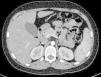

En la tomografía computada de tórax y abdomen se observaron conglomerados ganglionares en mediastino, mesenterio, retroperitoneo y región inguinal, infiltrado micronodular difuso bilateral, hepatomegalia, esplenomegalia, así como litiasis renal derecha (fig. 3).

3DiscusiónEl presente caso corresponde a un adolescente de sexo masculino con un cuadro clínico compatible con sarcoidosis infantil de inicio tardío, con grave afección del estado general que le llevó a la caquexia. También presentaba daño pulmonar, hepatomegalia, esplenomegalia, adenopatías múltiples, eritema nodoso y masa escrotal. Se realizó el protocolo de abordaje diagnóstico para pacientes con hepato-esplenomegalia, el cual permitió descartar varias enfermedades infecciosas, como tuberculosis, micosis sistémicas, sífilis e infección por virus Epstein Barr (VEB) y virus de la inmunodeficiencia humana (VIH), además de otras causas de síndrome infiltrativo, como leucemias, linfomas, tumores metastásicos y linfohistiocitosis hemofagocítica, mediante los estudios de tomografía computada y las biopsias de médula ósea y de ganglio linfático. Se descartaron, incluso, vasculitis sistémicas y otras enfermedades autoinmunes, así como los tumores testiculares de la adolescencia con base en los hallazgos del ultrasonido testicular y con los niveles normales de marcadores tumorales como alfa-feto proteína y beta-gonadotropina61.

A su ingreso se detectó insuficiencia respiratoria crónica tipo I, sin repercusión cardiovascular, con hipoxemia, normocapnia e hiperlactatemia. La radiografía de tórax mostró infiltrado micronodular y reticular difuso con adenopatías hiliares bilaterales, concordante con el Estadio II de la clasificación de la American Thoracic Society para sarcoidosis torácica. Así mismo, la espirometría y la pletismografía reportaron una disminución de la relación VEF1/FVC, compatible con una neumopatía de patrón restrictivo leve como se ha descrito en las dos primeras etapas de la sarcoidosis pulmonar, que se normalizó después del tratamiento con prednisona.